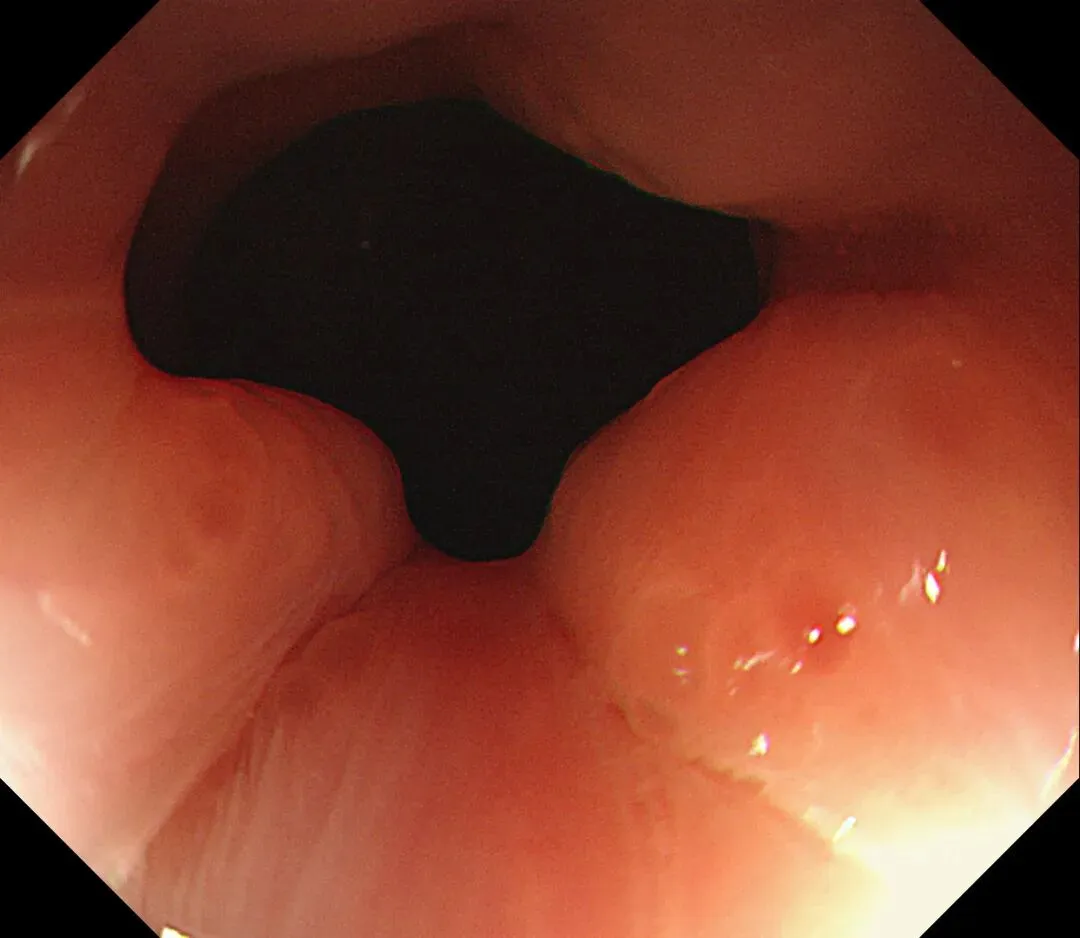

进镜至贲门观察到“花环征”,提示存在AIG的可能,带学生的内镜老师这个moment可以装一把,不过。。。偶尔也有翻车的时候,以下这例是在“Hp现症感染C3萎缩”患者的花环

有待进一步研究。。。